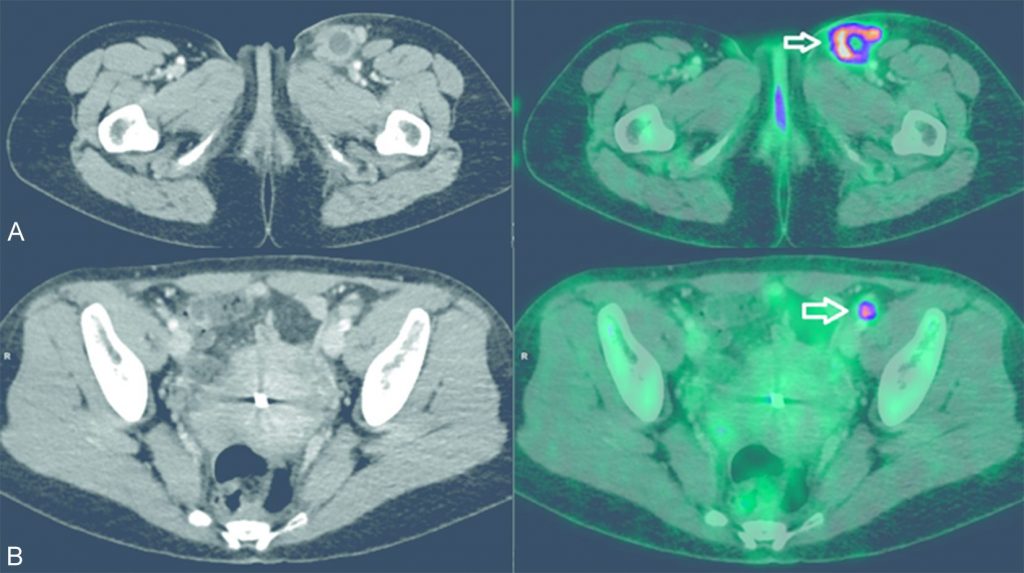

- la TEP au 18FDG est recommandée dans le bilan d’extension initial du mélanome à partir du stade III (figure 44.1).

Fig. 44.1. Images TDM (à gauche) et TEP au 18FDG fusionnée à la TDM (à droite) en coupes axiales.Elles sont réalisées pour un bilan d’extension initial d’un mélanome cutané ulcéré du versant latéral de la cuisse gauche, retrouvant un hypermétabolisme suspect d’une adénomégalie nécrotique fémorale superficielle gauche (A) et d’une formation lymphatique infracentimétrique iliaque externe gauche (B).

Source : CERF, CNEBMN, 2022.